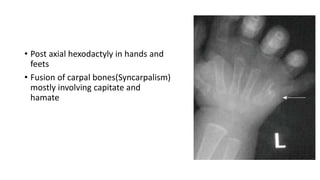

• Post axial hexodactyly in hands and

feets

• Fusion of carpal bones(Syncarpalism)

mostly involving capitate and

hamate